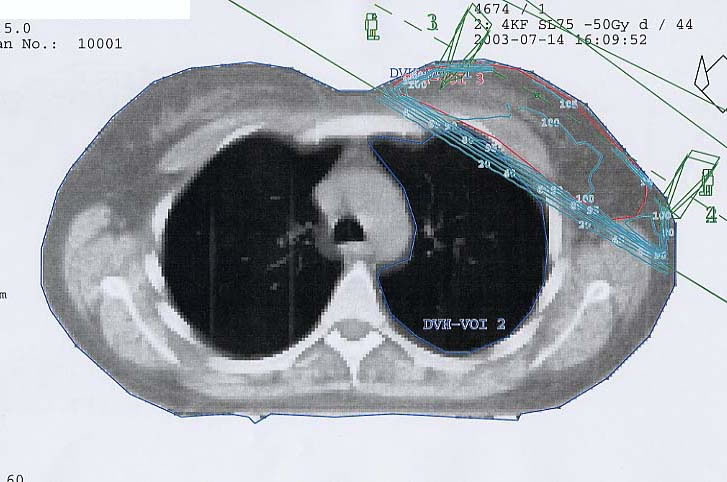

Mammakarzinom: Bestrahlungsplan

Bestrahlungspläne